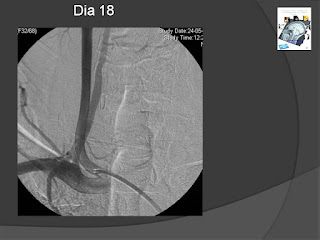

A nível do disco C7/D1 existência de uma espinha óssea epidural anterior mediana com cerca de 3,5 mm provocando eventualmente laceração meningea.

CT Study reveled at the C7/T1 level the existence of an epidural spinal median bone of about 3.5 mm, possibly causing meningeal laceration.